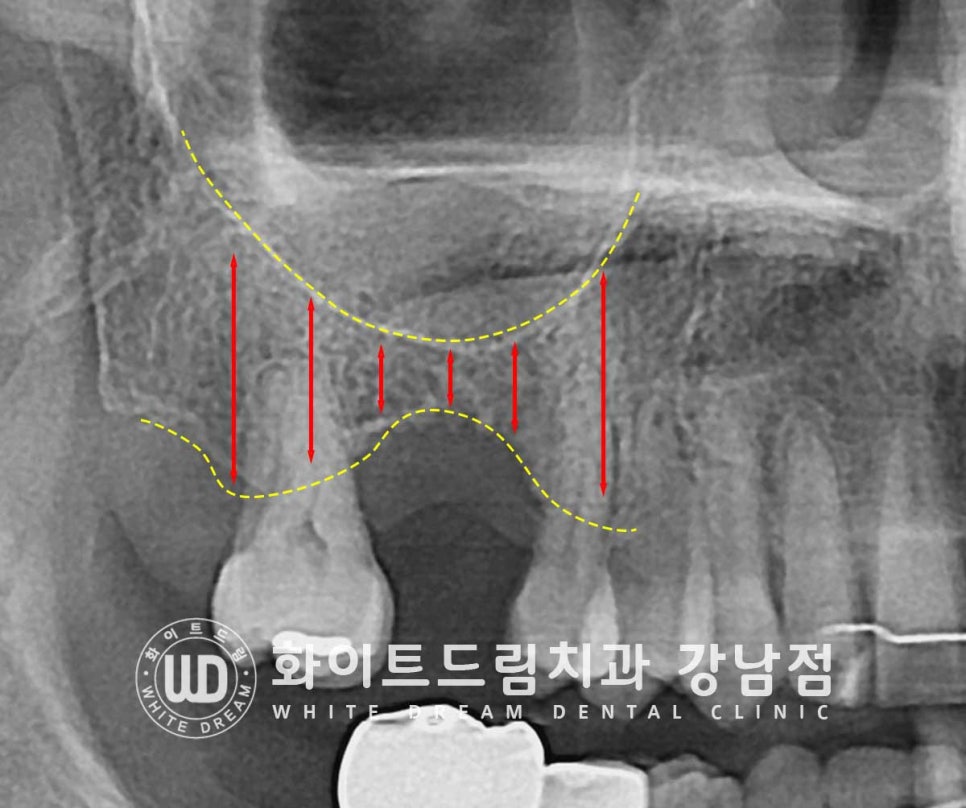

이렇게 잇몸뼈가 없을 때 뼈이식을 동반하여 모자란 잇몸뼈를 형성해 주게 되는데

상악 어금니에는 하악 & 앞니와 조금 다른 뼈이식 술식이 진행됩니다.

바로 '상악동 거상술'인데요.

상악 어금니 위쪽에는 상악동이라는 탁구공만 한 빈 공간이 있습니다.

코와 연결되어 있기에 공기가 오고 가고, 이물질은 코로 배출이 됩니다.

상악 어금니를 발치하고 임플란트를 진행할 때

이렇게 환자분처럼 잇몸뼈가 많이 부족하면 임플란트가 상악동 내부로 빠지거나

상악동의 얇은 막이 뚫려버리는 천공이 나타날 수 있습니다.

이럴 때 많이 진행하는 상악동 거상술이 바로 '측방 접근법'이라는 술식입니다.

상악동을 4mm 이상 크게 들어 올려야 할 때 진행하는 술식으로